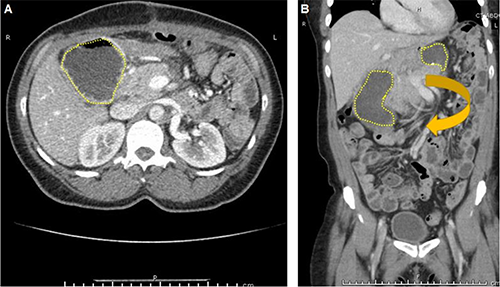

A contrast-enhanced computed tomography (CT) scan showed that the stomach was coursing along the right side of the abdomen (Figure 1A) and was obstructed (Figure 1B) up to the junction with the duodenum. This was concerning for an organoaxial gastric volvulus.

Figure 1. A CT scan of the patient on the day of her presentation to a routine clinic appointment, 13 days after her laparoscopic DPS. A: On transverse sections of the CT scan, the stomach is seen to be abnormally present on the right side of the abdomen (yellow-dashed line). B: On coronal sections of the CT scan, the stomach is imaged with both the cranial portion visible to the left of midline and the caudal portion visible to the right of the midline (both outlined in yellow dashes) with an arrow denoting the direction of volvulus.